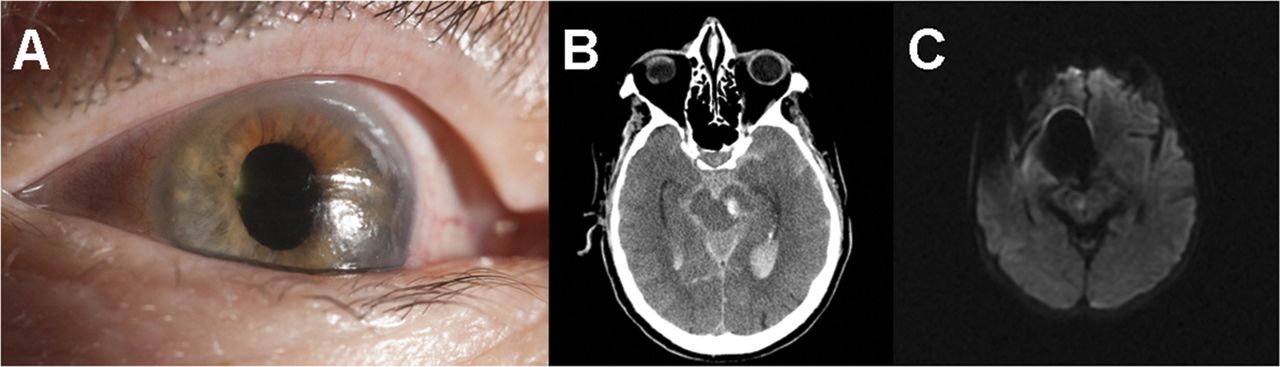

一个79岁的老人与一个无症状左颈动脉狭窄后立即进入昏迷左颈动脉支架。他有一个手术,圆的,7毫米,无反应的瞳孔,和一个椭圆形,6×5毫米,无反应的瞳孔(图,一个)。CT显示左侧中脑内急性出血花梗与蛛网膜下腔和脑室内出血(修改费舍尔规模4级)(图B)。接下来的一个小时里,他失去了所有脑干反射除了自主呼吸,持续了18个小时。他成为了脑死亡后,椭圆形配置呆了36个小时。